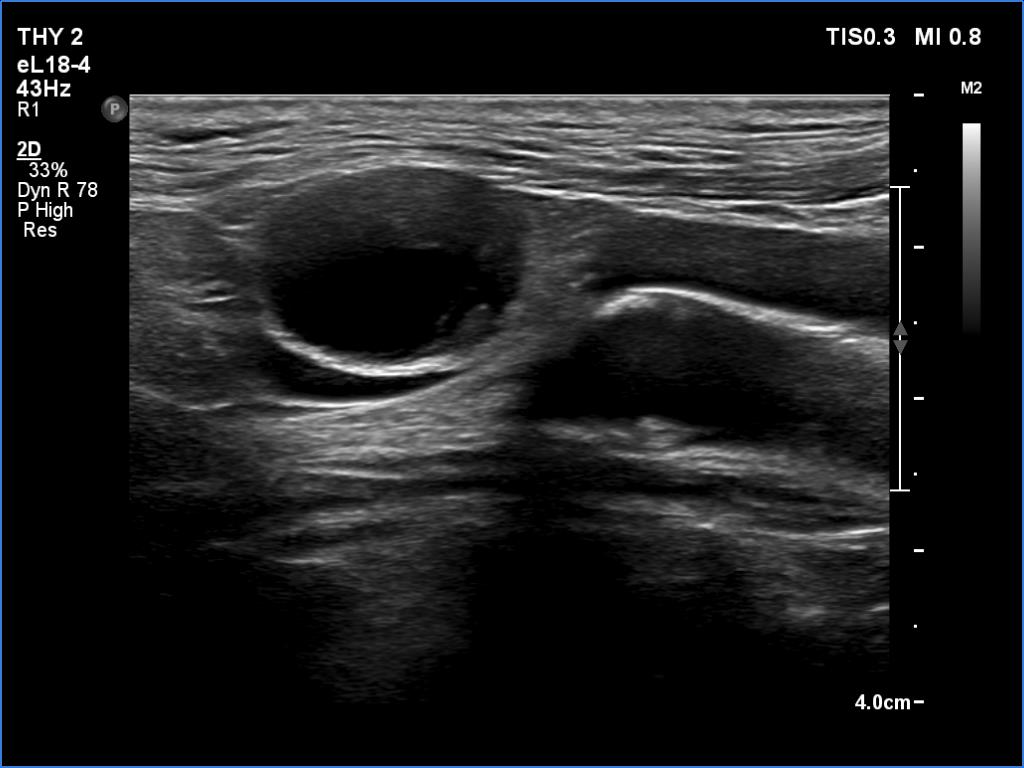

Ultrasonography. The right lobe was echonormal and intact. A large mass occupied almost the entire left lobe. On this side, normal thyroid tissue could only be identified in the dorsal part. The mass was composed of echonormal and hypoechoic areas, had macrocalcifications, irregular intranodular vascularity and proved to be very hard on elastography. There were multiple lymph nodes in III, IV and V left neck compartments. One of the nodes was in close proximity to the jugular vein and was suspicious of having broken into the vessel. The trachea was significantly narrowed at the lower level of the thyroid.

2. There are several remarkable findings in this case, e.g., the destruction of the left lobe by the tumor, the elastography pattern, the relation of the largest metastatic lymph node and the jugular vein, the ultrasound demonstration of the trachea' stricture.